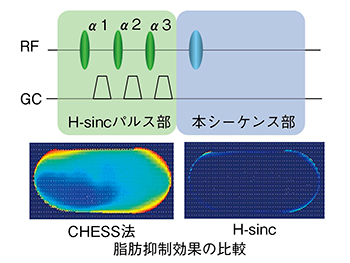

■最適化脂肪抑制法:H-sinc

脂肪信号の抑制技術は,特に高磁場MRIにおいて重要な技術である。IRシーケンスの脂肪null pointを利用するshort TI inversion recovery(以下,STIR)法と,事前に脂肪のみを選択的に照射して抑制するchemical shift selective(以下,CHESS)法以外に,独自に開発した脂肪抑制RFパルス“H-sinc”を搭載した。

H-sincはRF照射における不均一の影響が少ないという特長があり,特に腹部など撮像視野の大きな場合に画像周辺部で高い効果がある。この技術は,図3に示すように,CHESSパルスを複数回に分割して印加し,さらにその印加タイミングやパルス強度を最適化して使用することで,安定した脂肪抑制効果を得るものである。

図3に,ファントムによるH-sincの脂肪抑制結果を示す。H-sincではRFの不均一に敏感なCHESS法と比較して安定して広範囲で高い脂肪抑制効果が得られており,磁化率による不均一の影響を受けやすい領域においても良好な脂肪抑制画像が期待できる。

図3 最適化脂肪抑制法H-sinc